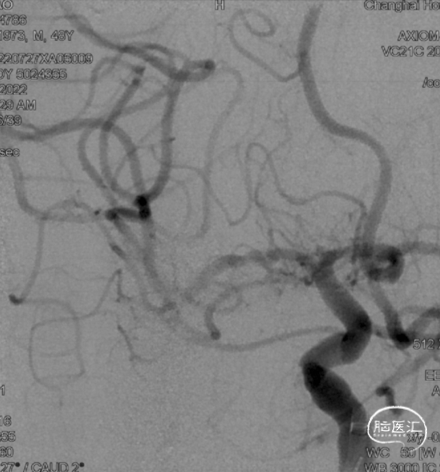

复查脑血管造影示:右侧大脑中动脉支架置入术后,支架位置良好,管腔内血流通畅,未见明显狭窄。

术后2年随访:

复查脑血管造影示:右侧大脑中动脉支架置入术后恢复良好,支架位置精确无误,其管腔血流通畅,未见任何明显狭窄,手术效果满意。

2024-08-07 2Y-FU (正位)

2024-08-07 2Y-FU (侧位)